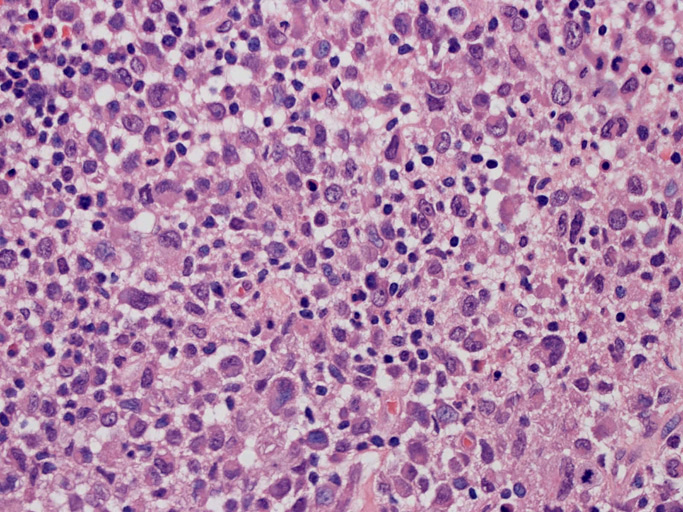

大型細胞の増殖よりなる腫瘍。縦溝,しわ,切れ込みのある核をもった大型細胞も出現する。クロマチンは顆粒状で核小体も明瞭である。核分裂は >50/10hpfと多い。eosinophilsは少ない。壊死が多発することがある。未分化ないし低分化な細胞像, 組織所見のため鑑別診断は多岐にわたり、的確な免疫染色を行う必要がある。

皮膚に異型細胞の浸潤がみられる。異型細胞は表皮内に浸潤するほか、表皮真皮境界部, 真皮, 皮下脂肪組織にもびまん, 結節様の浸潤所見を示す。血管周囲に浸潤、集蔟する所見も多く見られる。 増殖浸潤細胞の核には類円形や腎臓形, またはへこみ, 切れ込み, 溝などを有する多型な核が認められる。クロマチンは粗でvesicularな核が多い。核小体の明らかな核もある。好エオジン性の核内封入体様構造も少数に見られた。mitosisは容易に認められる。hyperchromaticな多型核, bizzarreな細胞が高頻度に認められ異型度は高いと考えられる。細胞質は境界不明瞭, 淡明または泡沫様の 好エオジン性胞体である。